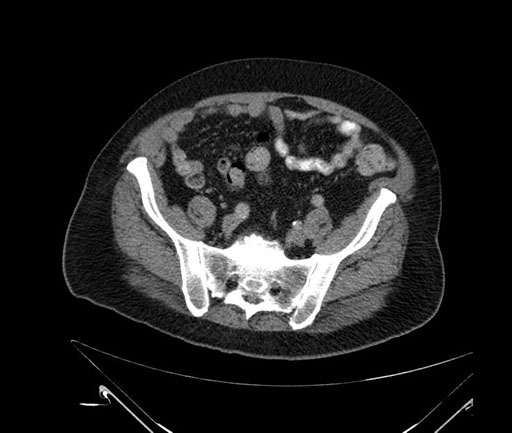

Axial - stented